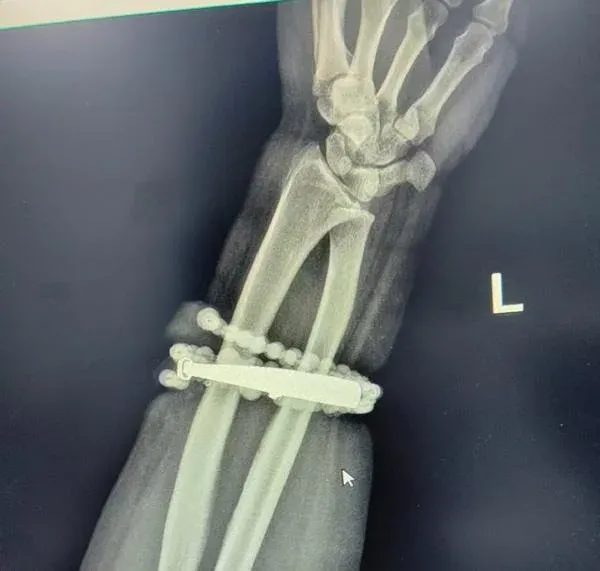

หญิงวัย 33 ปี ชาวเมืองหนิงเต๋อ มณฑลฝูเจี้ยน ประเทศจีน ต้องเข้ารับการผ่าตัดอย่างเร่งด่วน หลังจากที่กำไลเงินและลูกประคำที่เธอ สวมไว้ที่ข้อมือมานานกว่า 10 ปี ค่อยๆฝังลึกเข้าไปในเนื้อแขนของเธอ เนื่องจากน้ำหนักตัวที่เพิ่มขึ้น จนเกิดการติดเชื้ออย่างรุนแรง แพทย์ใช้เวลากว่า 1 ชั่วโมง ในการผ่าตัดนำเครื่องประดับออกและทำความสะอาดบาดแผล ซึ่งช่วยให้เธอรอดพ้นจากการถูกตัดแขน

แพทย์กล่าวว่า "หญิงรายนี้สวมกำไลเงินและลูกประคำไว้ที่ข้อมือ มาตั้งแต่เมื่อ 10 ปีก่อน โดยแทบไม่เคยถอดออกเลย กระทั่งช่วงหลังมานี้ น้ำหนักตัวของเธอเพิ่มขึ้น ทำให้เธอรู้สึกว่ากำไลเริ่มแน่นขึ้น แต่เพราะยังรู้สึกเพียงเล็กน้อยจึงไม่ได้ใส่ใจ ต่อมาในช่วงครึ่งปีที่ผ่านมา ข้อมือเริ่มมีอาการบวม แดง และคัน เธอคิดว่าเป็นเพียงผื่นผิวหนังทั่วไปจึงไปซื้อยามาทาเอง แต่ในช่วง 2 สัปดาห์ล่าสุดกลับเริ่มปวดอย่างรุนแรง มีหนองไหลออกมา และพบว่ากำไลกับลูกประคำ ได้ฝังลึกเข้าไปในเนื้อจนไม่สามารถถอดออกได้" และ "หลังเข้ารับการรักษาอย่างเร่งด่วน เราพบว่าเนื้อบริเวณข้อมือของเธอ มีอาการอักเสบเรื้อรังและเกิดเนื้อเยื่อใหม่ผิดปกติ จากการระคายเคืองต่อเนื่อง กำไลจึงกลายเป็นจุดก่อการติดเชื้อ หากปล่อยไว้การอักเสบอาจลุกลามไปถึงทั้งแขน"

หลังจากที่แพทย์ใช้เวลากว่า 1 ชั่วโมงในการผ่าตัด แพทย์สามารถนำเครื่องประดับที่ฝังอยู่ใต้ผิวหนังออกได้ทั้งหมด พร้อมทำความสะอาดและควบคุมการติดเชื้อได้สำเร็จ ปัจจุบันหญิงรายนี้อาการดีขึ้นและออกจากโรงพยาบาลแล้ว